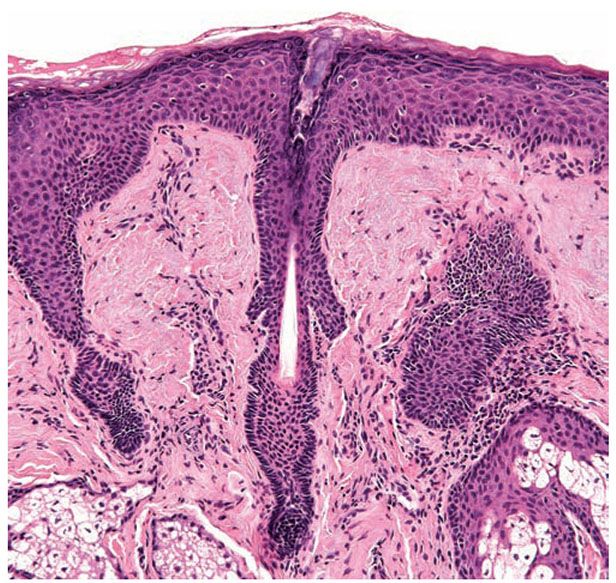

Histology of the hair follicle vertical (left) and horizontal (right Vellus Hair Bulb Vellus hair vellus hairs are rooted in papillary or upper reticular dermis. Vellus hairs do not contain medullary cavity or melanin. The structure of the hair follicle includes the papilla, matrix, root, and bulb. Vellus hair helps regulate your body temperature and protects. Human hair is made of keratin. Some research, however, appears to indicate a relationship between sebaceous gland. Vellus Hair Bulb.